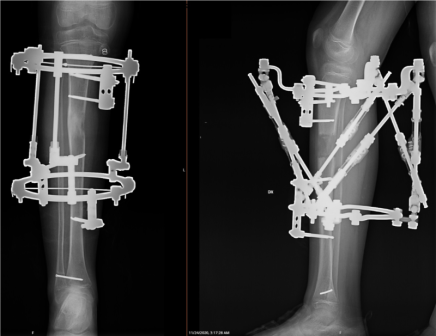

Gan iedzimtu, gan iegūtu ekstremitāšu deformāciju un asimetriju ir iespējams labot ar estētiskās ortopēdijas un deformāciju korekcijas palīdzību. Korekciju iespējams veikt gan bērnībā, gan pieaugušā vecumā. Korekcijas nepieciešamību konsultācijas laikā izvērtē speciālists.

Operācijas ilgums: līdz 2 stundām, izmantojot spinālo vai pilno anestēziju, uzturēšanās klīnikā – viena diennakts.

Atkārtota vizīte: 7 dienas pēc operācijas. Konsultācijas laikā tiek veiktas pārbaudes, mērījumi un sniegta informācija par ārējas fiksācijas aparāta regulēšanu mājas apstākļos.

Korekcijai nepieciešamais laiks: vidēji 3-4 mēneši no operācijas brīža līdz ārējās fiksācijas aparāta noņemšanai.

Palīglīdzekļi: Kruķi. Pakāpeniski palielinot slodzi, pacients sāk pārvietoties patstāvīgi. Pēc operācijas jāievēro saudzējošais režīms.